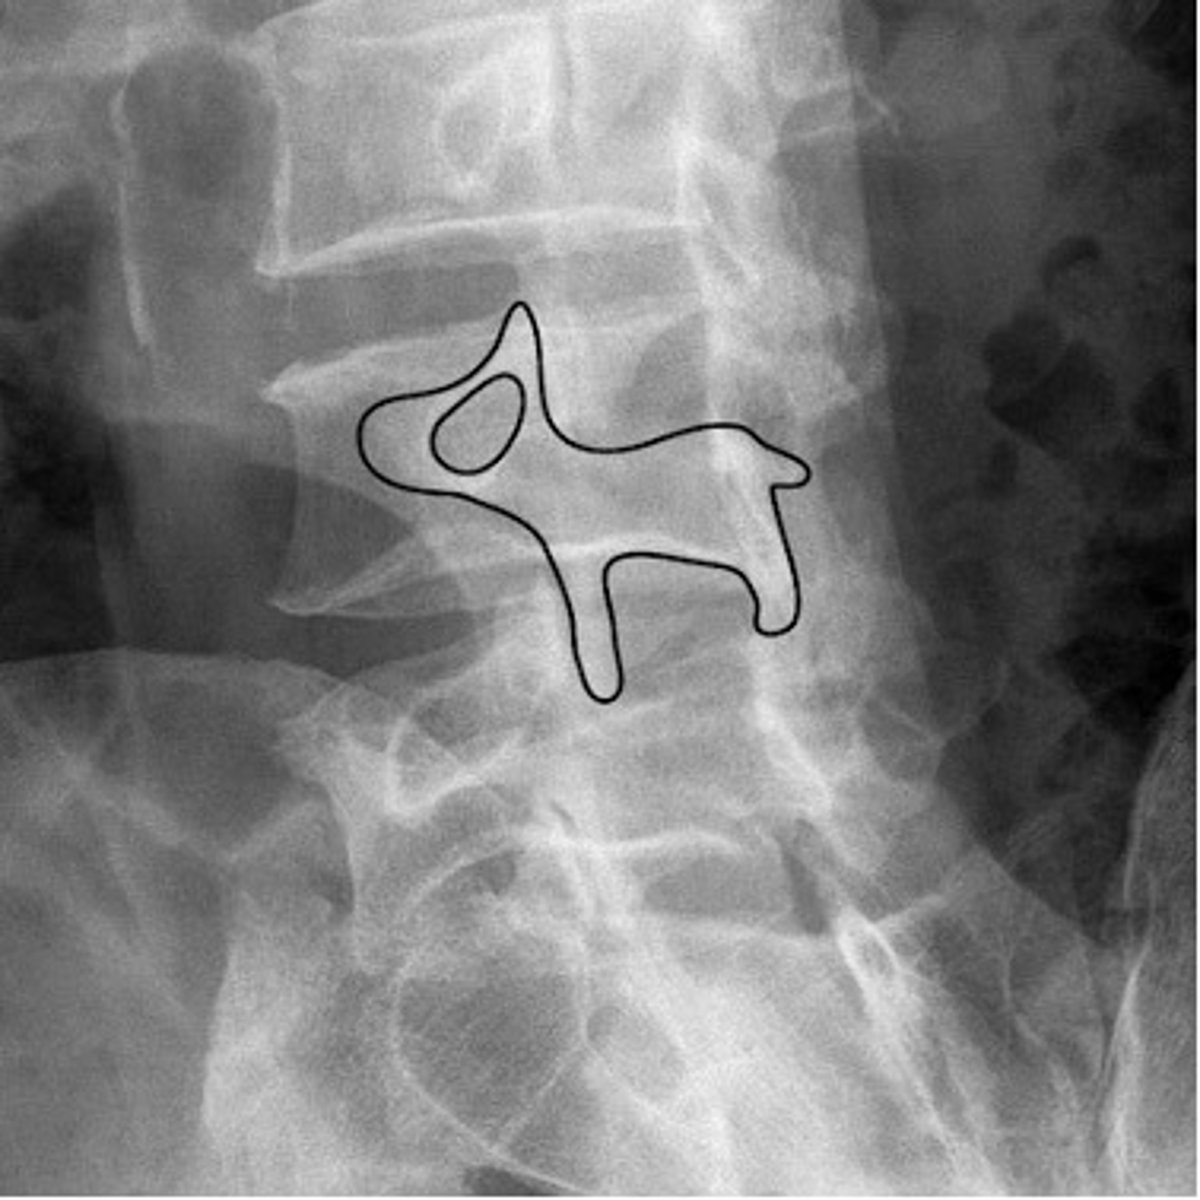

scottie dog

nose- transverse process

eye- pedicle

ear- superior articular facet

front leg- inferior articular facet

neck- pars interarticularis